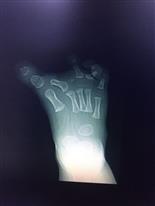

تصوير الأطراف السفلية بالأشعة السينية، لتحري وجود خلل في عظمة الظنبوب أو وجود أي أعراض أخرى للمرض.